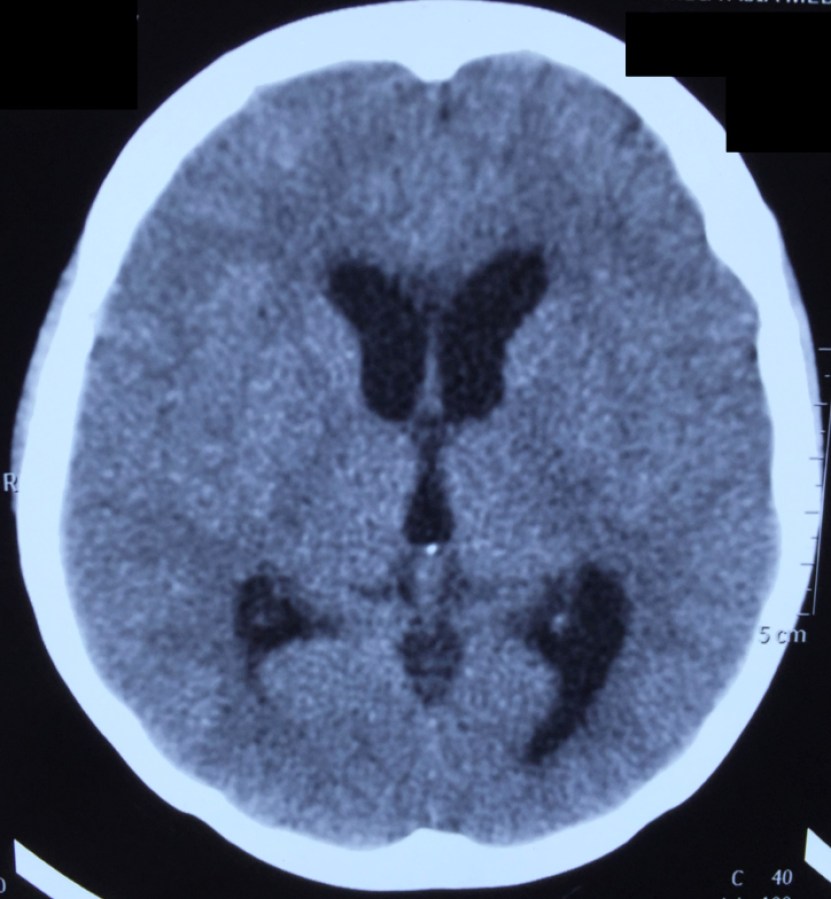

CT-head-2